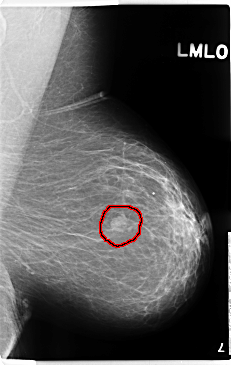

C_0210_1.LEFT_MLO

FILE: C_0210_1.LEFT_MLO.OVERLAY

TOTAL_ABNORMALITIES 1

ABNORMALITY 1

LESION_TYPE MASS SHAPE OVAL MARGINS MICROLOBULATED

ASSESSMENT 4

SUBTLETY 5

PATHOLOGY MALIGNANT

TOTAL_OUTLINES 1

BOUNDARY